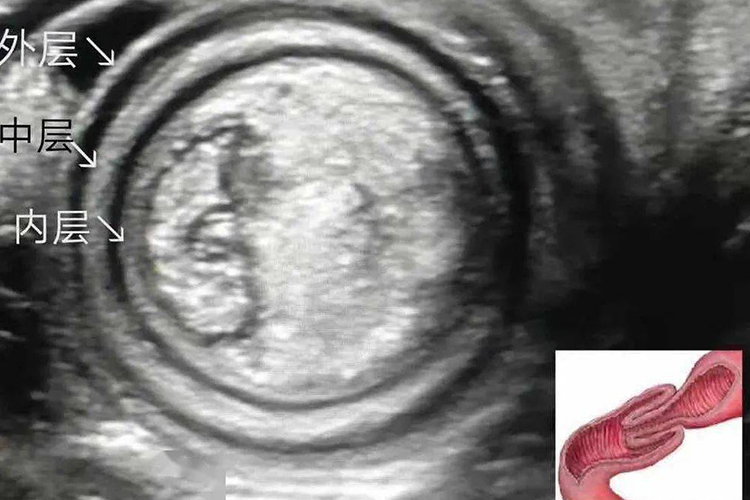

肠套叠杯口征是指肠套叠时钡剂或空气灌肠检查时可显示套头梗阻端所形成的杯口状。

肠套叠杯口征是指在X线透视下,经肛门插管注入钡剂,钡剂到达套入部通过受阻,钡首呈杯口状或球形充盈缺损。肠套叠腹部平片表现小肠梗阻征象,肠管内可见阶梯状气液平面。肠套叠的临床表现常见腹痛、呕吐、便血及腹部包块,还可并发肠坏死和腹膜炎。

肠套叠指部分肠管及其肠系膜套入邻近肠腔所致的一种肠梗阻,是婴幼儿时期常见的急腹症之一。婴儿回盲部系膜尚未完全固定活动度较大是容易发生肠套叠的结构上因素。此外,发生肠套叠的肠管多有明显的器质性原因,如梅克尔憩室翻入回肠腔内,成为肠套叠的起点。肠息肉、肠肿瘤、肠重复畸形、腹型紫癜致肠壁肿胀增厚等均可牵引肠壁发生肠套叠,进行钡剂或空气灌肠检查时可出现杯口征。